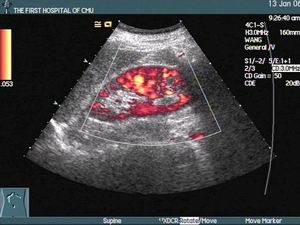

4.超聲心動圖對評價舒張性心力衰竭最有價值,可提供心臟結構和功能異常的重要線索:

①結構上,可發現左心室形態異常,如高血壓、主動脈瓣狹窄等所致的向心性肥厚;肥厚型心肌病所致的非對稱性肥厚;老年患者可呈現小心腔、室壁中度增厚,即室間隔上部突入左心室流出道,甚至構成狹窄;浸潤性心肌病,特別是心臟澱粉樣變,可顯示雙心室室壁增厚、左心室室壁對稱性增厚、心肌呈斑點狀回聲等組織特徵;右室壓或容量負荷過重可致室間隔左移和右心室呈幾何形態改變。舒張性心力衰竭患者儘管左心室腔正常或變小,但左心房常有不同程度的增大。

②功能上,舒張性心力衰竭患者的收縮功能一般良好,左心室射血分數(LVEF)大多正常,部分肥厚型心肌病患者LVEF超過70%。用M型超聲心動圖檢測二尖瓣前葉曲線的E峰、A峰峰值可用於判斷左心室舒張功能,E/A比值<1提示左心室舒張功能減退。都卜勒測定二尖瓣血流頻譜是評價舒張功能的簡單易行的常用方法,可揭示左心室舒張功能異常及其進展過程。舒張早期流速峰值(EPFV)、舒張晚期血流值(APFV)、舒張早晚期流速峰值比(EPFV/APFV)及舒張早期峰速減速度(DC)都是常用的指標。舒張性心力衰竭患者的EPFV、DC減低,APFV增高,EPFV/APFV小於1。此外,當左心室鬆弛性減退時,等容舒張時間(IVRT)延長;當左心室僵硬度增加時,IVRT縮短;當左心室鬆弛性和僵硬度均有異常時,二尖瓣血流頻譜可“偽正常化”。高齡、心率加快(大於90次/min)、左心室前負荷減小或後負荷增加時可出現假陽性。房室平面位移(atrioventricularplanedisplacement,AVPD)的測定最初用於評價收縮功能,方法是用M型超聲在心尖四腔觀中室間隔與二尖瓣前葉交界點、左心室側壁與二尖瓣後葉交界點位處和在心尖二腔觀中左心室前、後壁與二尖瓣葉的交界處等四個部位記錄收縮期房室平面的最大位移程度。1992年Alam等用AVPD法評價左心室舒張功能,發現左心室舒張功能異常患者時常表現為心房收縮所致的AVPD值在總的AVPD值中所占的比例增高,且這種改變與用脈衝都卜勒測量二尖瓣血流頻譜所得的A/E比值改變有良好相關。

肺靜脈血流頻譜分析也有助於評價左心室舒張功能。多數正常人肺靜脈血流頻譜為三相峰,由收縮峰(S)、舒張峰(D)及心房收縮峰(A)組成。正常時S低於D,但測值接近(參考值為0.55m/s);A很小,約為0.18m/s。左心室舒張功能異常的患者表現為右上肺靜脈血流頻譜S值升高、D值降低、S/D比值增加、A值升高,這種異常與左心室結構和功能密切相關。聲學定量(AQ)方法通過自動檢測心內膜邊界得出左心室面積隨時間變化的曲線及面積變化率(dA/dt)隨時間變化的曲線。後者為雙峰形態,即舒張早期峰值充盈率與舒張晚期充盈率。脈衝都卜勒超聲測量二尖瓣血流頻譜可以發現,E/A比值下降,而AQ方法可發現峰值充盈率/晚期充盈率比值下降。在有些無左心室肥厚的輕度高血壓患者,脈衝都卜勒超聲左心室充盈參數在正常範圍,而AQ方法可檢出E峰加速時間(AT)延長及早期充盈時間延長。脈衝都卜勒心肌顯像(DMI)技術通過在不同心肌節段放置取樣容積以進行在機定量分析,可檢出不同心肌節段受損的範圍和程度。舒張功能不全累及的心肌節段越多,左心室整體舒張功能的損害越大。另外,可用負荷試驗來提高早期舒張功能異常患者的檢出率,例如握力超聲心動圖試驗可用於高血壓患者潛在性舒張功能異常和心肌缺血的診斷。超聲心動圖對左心室舒張功能的檢測結果受許多因素如取樣容積的部位、聲速與血流方向的夾角、年齡、生化和代謝因素(血漿腦利鈉肽、血漿心房利鈉肽等)、藥物如血管緊張素轉換酶(ACE)抑制藥等的影響,故必須結合臨床、心臟形態及功能等資料進行綜合分析。